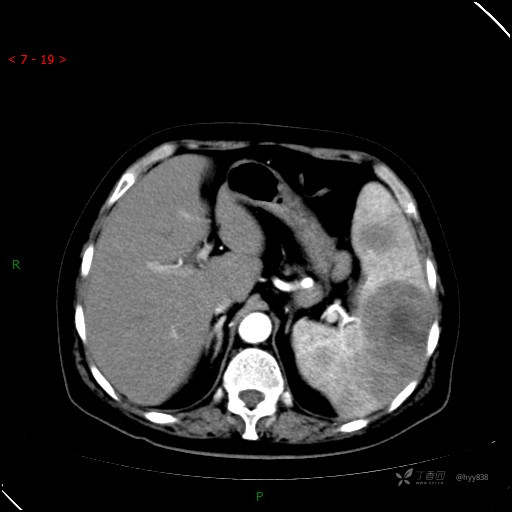

上腹部CT平扫